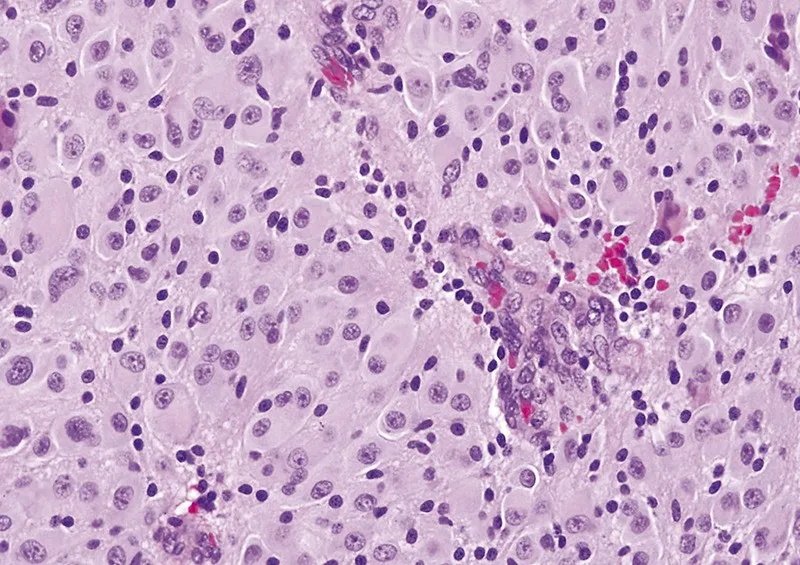

室管膜下巨细胞星形细胞瘤属于边界清楚的星形细胞瘤,属WHO 1级。室管膜下巨细胞星形细胞瘤常为伴发于结节性硬化的少见良性星形细胞肿瘤.占结节性硬化患者的10%~15%,病理学特征为由巨噬细胞样星形细胞构成的室管膜下巨细胞星形细胞瘤与结节性硬化和错构瘤共存。肉眼所见肿瘤为边界清楚的分叶状肿块,常见钙化、囊变和丰富的血管。镜下典型者呈双核或多核星形细胞瘤,常见囊变,分化良好,可见两核或多核形成,有丝分裂少见。

CNS WHO 1级命名不因有丝分裂活性(A)、少见的微血管增生(B)或坏死(即使栅栏状)(C)而改变。

CNS WHO 1级命名不因有丝分裂活性(A)而改变。

CNS WHO 1级命名不因少见的微血管增生(B)而改变。

CNS WHO 1级命名不因坏死(即使栅栏状)(C)而改变。